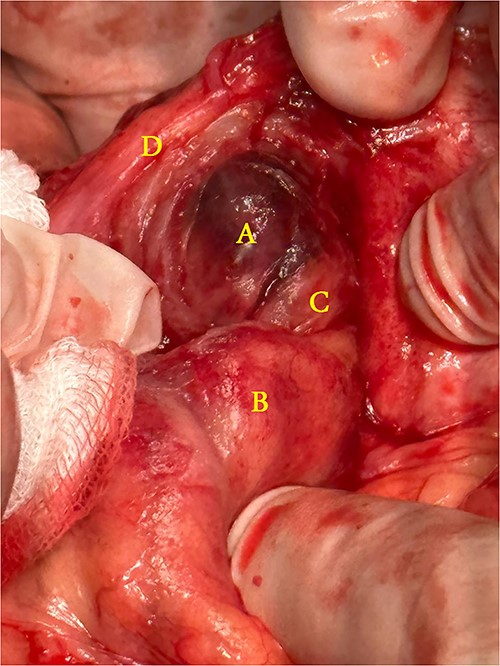

A 21-year-old male patient, obese with BMI of 35, known case of incisional hernia that occurred after an open appendectomy one year ago, was admitted to the emergency department complaining of acute abdominal pain for one-day duration. The pain was localized to the RLQ at the site of the incisional hernia, sudden in onset, sharp in character, not radiated with no known aggravating or relieving factors, and not associated with nausea, vomiting, abdominal distention, or change in bowel habit. On admission, he had normal vital signs. Physical examination showed a huge reducible incisional hernia in the RLQ area, at the McBurney scar with no signs of inflammation. There was significant tenderness at the McBurney point. Laboratory tests showed an increase in C-reactive protein (CRP) 180.00 g/l (0–5 g/l) and leukocyte count 17 000*109/L (4.3–10.8 × 109/L). Other Laboratory tests are all within normal. Abdomen CT scan with IV contrast (Fig. 1) demonstrated a large peritoneal defect containing cecum and terminal ileum associated with adjacent facial thickening, prominent lymph nodes, fat stranding, and 1.5*2 cm fatty density, no signs of bowel obstruction. The initial diagnosis consists of EA or early incarcerated hernia. Nasogastric decompression was done, and IV fluids and antibiotics were started. However, the pain gradually increased despite medical management. Because of the severity of the abdominal pain, a decision to proceed with surgical exploration was made. Under general anesthesia, a McBurney incision was done at the site of the incisional hernia. Intraoperatively (Fig. 2), a hernia sac was identified, and multiple aggregated gangrenous EA infarctions were excised (Fig. 3), then a hernioplasty was used to repair the hernial defect. The postoperative period was uneventful. The patient started a soft diet on Day 2 and was discharged from the hospital on Day 4. Histopathologic examination showed an aggregate of fatty-fibrous tissue with fat necrosis, surrounded by active inflammation confirming the diagnosis of EA.

Operative findings: (A) infarcted epiploic appendages, (B) cecum, (C) ascending colon, (D) hernial sac.